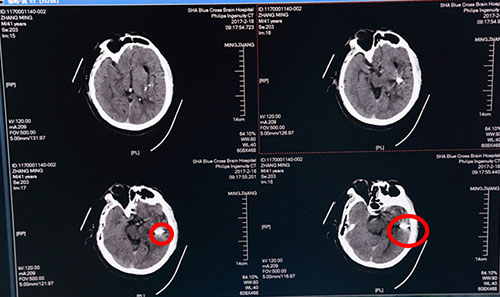

2月17日,张先生来蓝十字脑科就诊,并慕名找到李振并主任。此时距患者发病已6天,急查头颅CT示:1.左侧基底节区脑出血(急性期),部分蛛网膜下腔渗出;2.脑干、双侧基底节区腔隙灶,初步诊断为:高血压脑出血,运动性失语,肺部感染,高血压病III级(很高危),高血压性心脏病,II级糖尿病。考虑到患者病情不容耽搁,保守治疗效果不佳,两次出血35ML,有再出血可能,手术指征明确,征求家属意见后,遂决定紧急为张先生实施“颅内血肿微创清除术”进行治疗。

术前头颅CT:红圈内白色部分为脑出血血肿

当日,李振并主任急诊在局麻下为张先生施行了“颅内血肿微创清除术”。术中根据头颅CT片三维定位,取左侧颞部为穿刺点,用一次性血肿穿刺针直达血肿中心,接引流管,抽出暗红色血块40多ML。